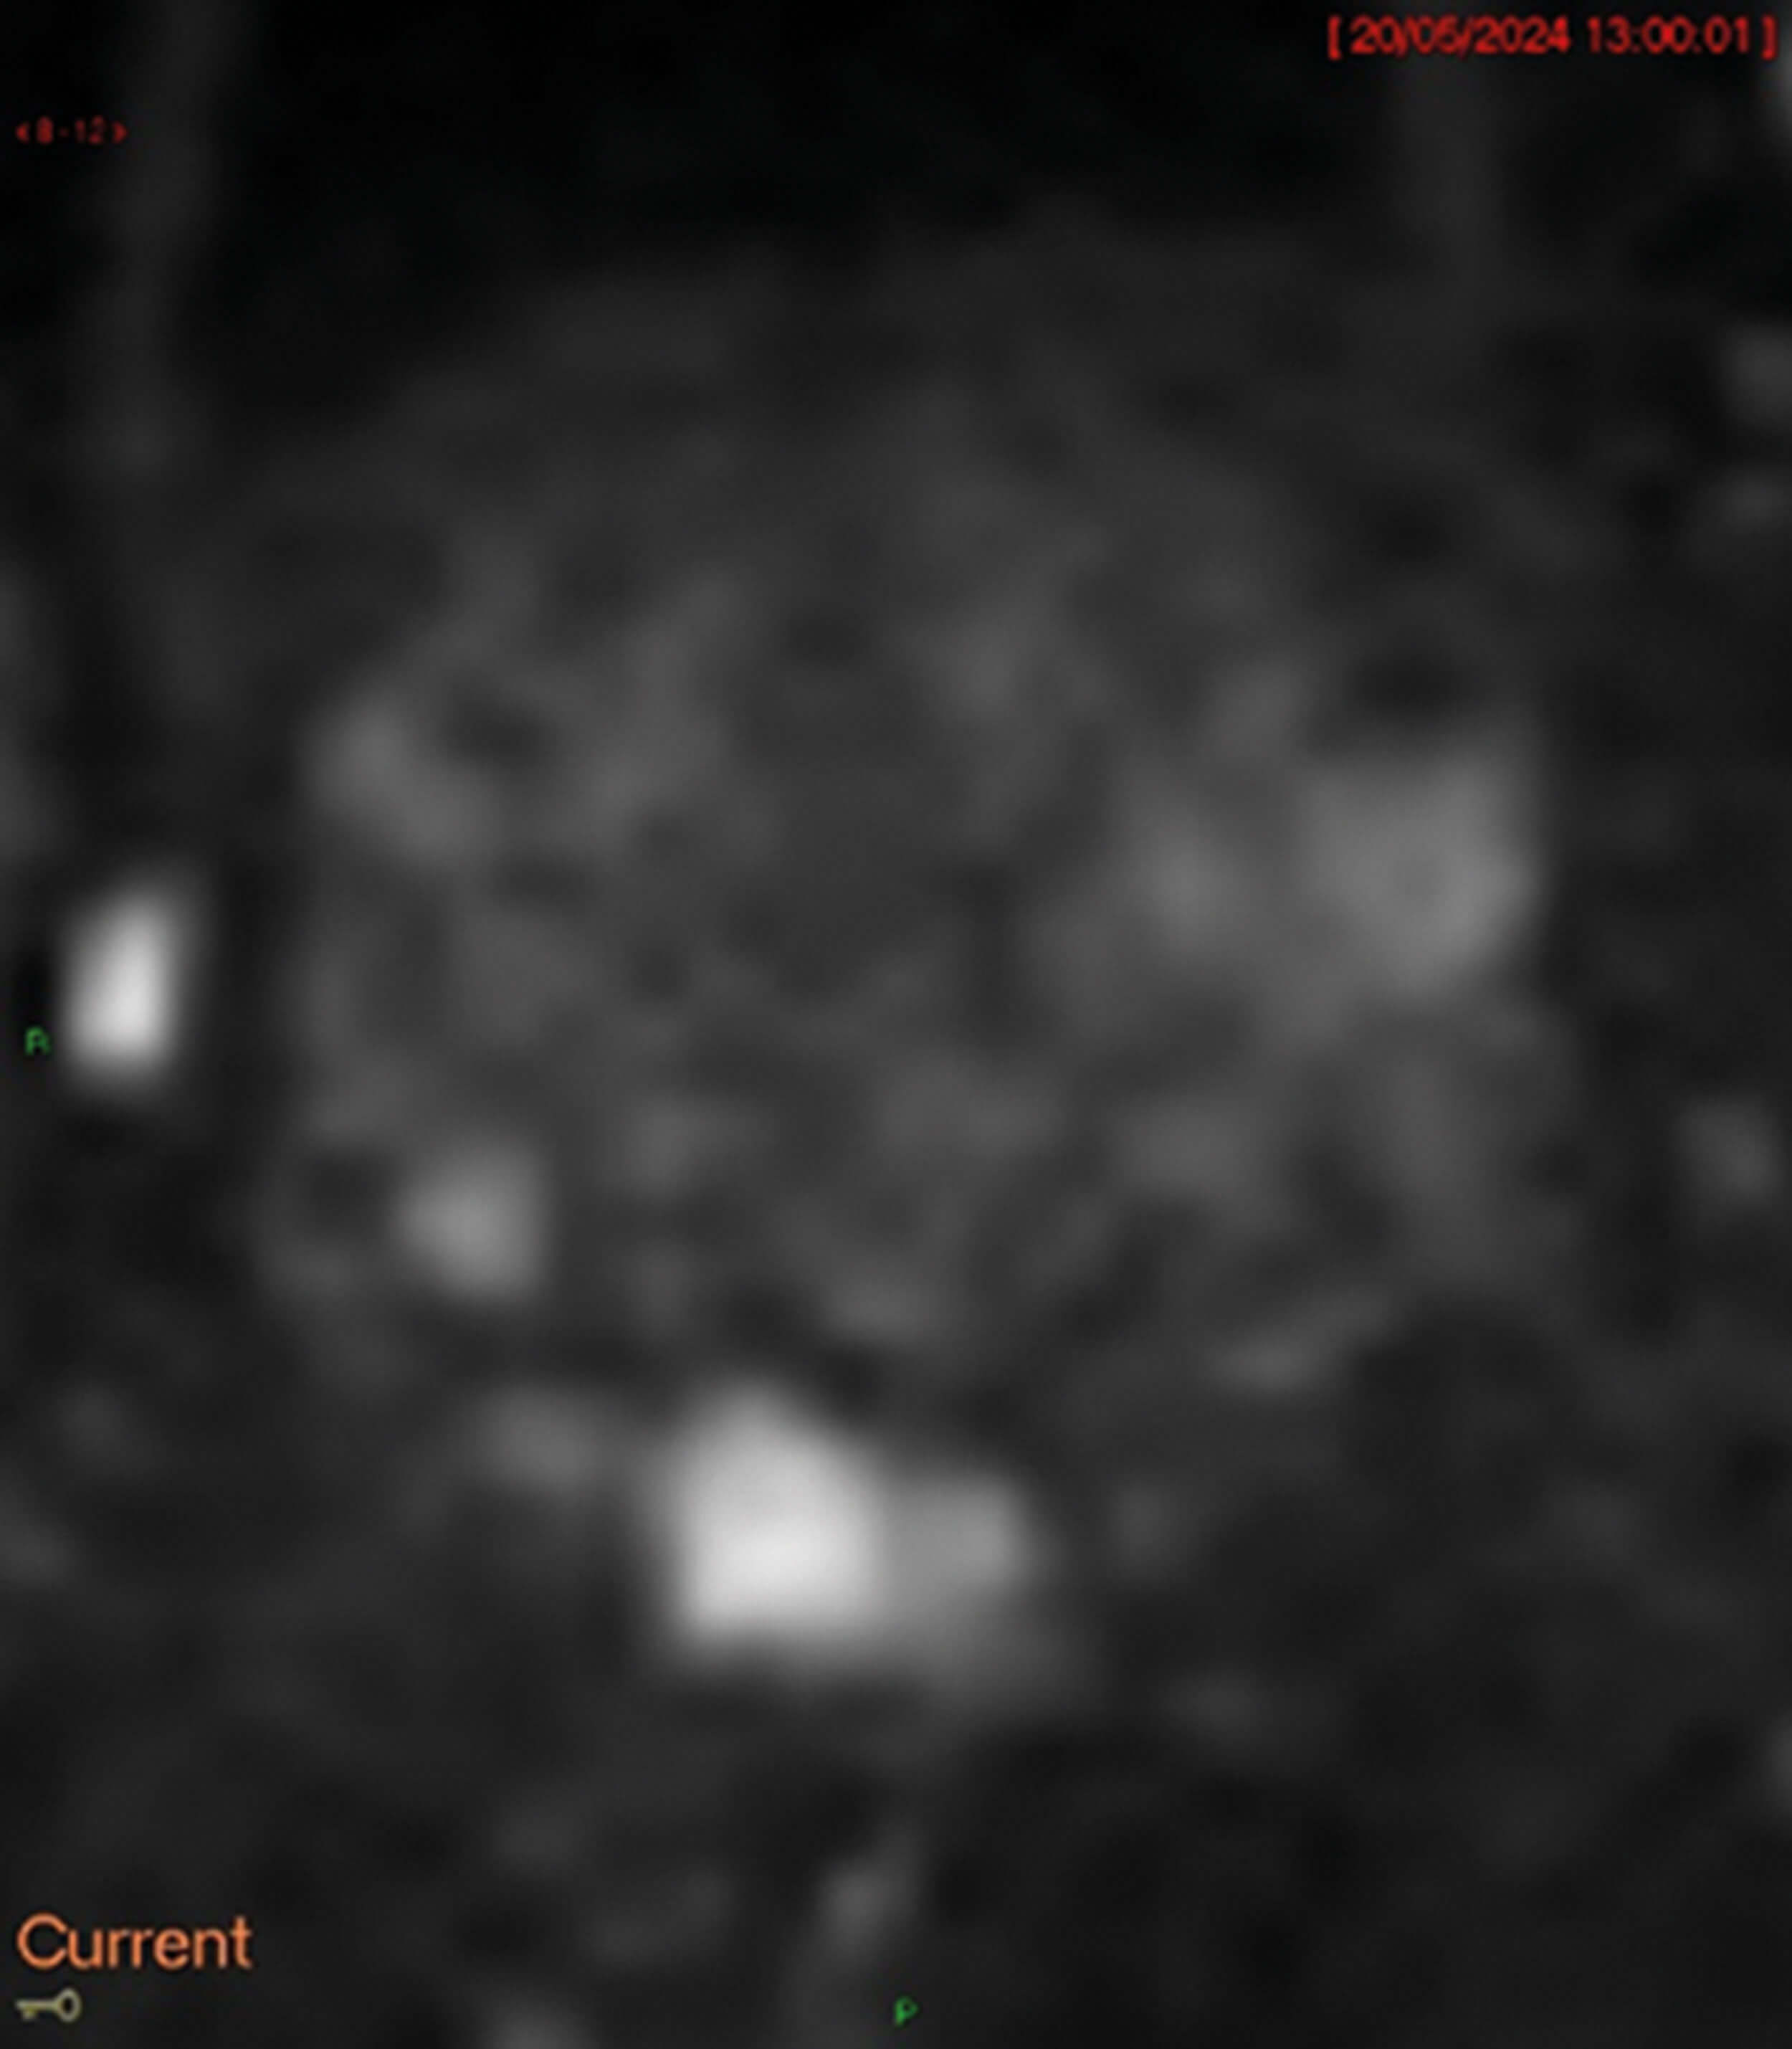

Figure 2.

- Figures 2-4 are the different MRI sequences. What sequences are they and what do they represent?

4. Diffusion weighted imaging (DWI, Figure 2) measures how easily water diffuses across cells, with restricted diffusion indicating increased cell density and tumour matrix.

Cancer typically appears bright on DWI (Figure 2) and darker on ADC (Figure 3) and radiologists compare sequences to check if they correlate.